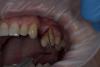

carloss Опубликовано 27 сентября, 2013 Поделиться Опубликовано 27 сентября, 2013 мне действительно хочется, не могли бы показать и указать на что обратить внимание. в общем как спланировать))Нужно чтобы корни были хотя бы средней длины, и выраженный без перегородок между корнями, что случается.. ещё желательно хорошо сохранившаяся дистальная и нёбный стенки, если есть и вестибулярная, то можно обойтись без вкладки.. срезать надо корень с прилегающей частью коронки, желательно, чтобы образовалась не очень вогнутая поверхность http://savepic.su/3393568.jpg http://savepic.su/3398688.jpg Ссылка на комментарий

Art 7 Опубликовано 27 сентября, 2013 Автор Поделиться Опубликовано 27 сентября, 2013 (изменено) там пломба объёмная но стенки думаю в полном поряде, и с длинной корней проблем нет вообще. теперь чисто практические вопросы если можно,?-отслаиваться вестибулярно надо?-прежде чем ампутировать надо очистить полость от пломбы чтобы визуализировать лучше? Изменено 27 сентября, 2013 пользователем Art 7 Ссылка на комментарий

carloss Опубликовано 27 сентября, 2013 Поделиться Опубликовано 27 сентября, 2013 там пломба объёмная но стенки думаю в полном поряде, и с длинной корней проблем нет вообще. теперь чисто практические вопросы если можно,?-отслаиваться вестибулярно надо?-прежде чем ампутировать надо очистить полость от пломбы чтобы визуализировать лучше?Отслаиваться вестибулярно, если только по по проекции ампутируемого корня, дистально лучше не провоцировать рецессии кости, может она там тонкая.. Полость желательно очистить, хотя можно срезать и с пломбой, сначала можно срезать поменьше, потом, при визуализации, можно доснять и хорошенько заполировать, обратите внимание, чтобы не осталось "заусенцев", а всё гладко переходило одно в другое.. лучше сразу временную коронку, которая прикрывает лунку корня 1 Ссылка на комментарий